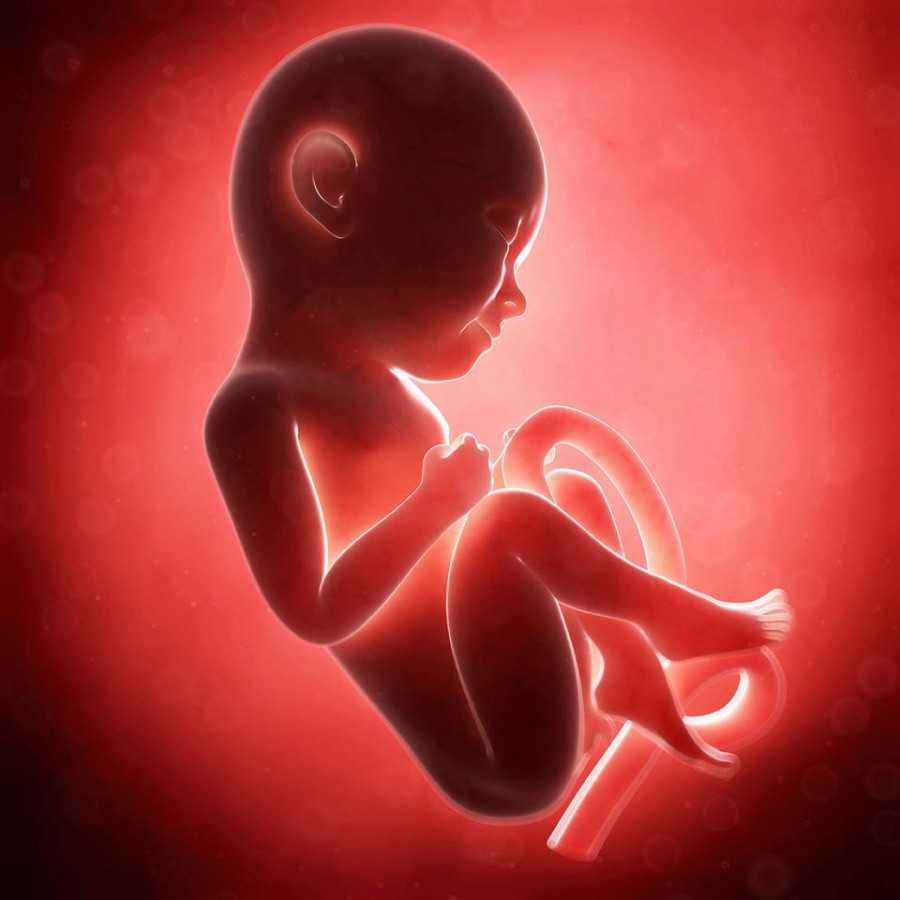

Плод на 9 неделе беременности и его развитие

Беременность 9–10 недель — это период очень активного развития ЦНС. Сформированы полушария головного мозга, закладывается мозжечок. Скоро движения малыша приобретут целенаправленность. Но уже сейчас он может двигать ручками, ножками, а если находится возле стенки матки — отталкивается от нее, как в бассейне. Малыш даже может совершать глотательные движения.

Происходит формирование спинномозговых ганглиев, нервных стволов. В головном мозге малыша закладывается гипофиз, он уже продуцирует гормоны.

Продолжается формирование сердца. Сейчас оно сокращается с частотой 130–150 ударов за минуту.

У эмбриона постепенно выпрямляется спинка, исчезает хвостик. Его головка склонена к туловищу, и пока она непривычно большая. Уже сформировались глазки малыша, но пока они закрыты веками. Еще не образованы свето- и цветочувствительные рецепторы сетчатки, они образуются на более поздних сроках.